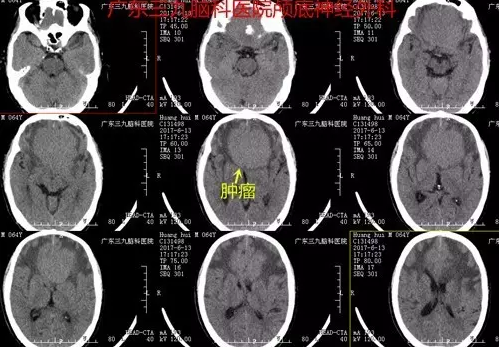

图1:术前CT提示额部类圆形稍高密度占位性病变

本例患者为老年男性,病程长,以头晕头痛就诊,伴恶心呕吐,未有明确定位症状,易误诊,行头颅CT及MR检查提示前颅窝底脑膜瘤。临床辅助检查中,头颅MR扫描对前颅窝底脑膜瘤的诊断意义最大。MRI 检查不仅可以显示肿瘤的体积及具体起源部位,而且还可以清楚显示肿瘤与邻近重要结构,如视神经、颈内动脉及其分支、垂体柄、下丘脑等的关系,这对指导手术人路的选择具有重要的意义。多数情况下前颅窝底脑膜瘤的MR增强扫描可见较均匀一致的强化,这与脑膜瘤的血运较丰富有关,有的情况下,如果肿瘤增强十分明显,而且肿瘤瘤内或周边有较多的血管流空,多提示肿瘤的供血血管较多,肿瘤血运丰富。本例患者术前CTA提示其内血供丰富,双侧大脑前动脉受压明显向右侧偏移,MR增强明显,其内见较多流空影,大小约5.9×6.3×3.5cm,体积巨大,且与嗅沟、视神经、垂体炳、下丘脑等关系密切,手术难度较大,术中行冠状切口经额予以全切除,切除时间约半小时,术中出血少,术后患者恢复快,术后严格监测血离子、尿量、垂体激素等的变化,术后患者出现一过性精神症状,目前恢复良好出院。